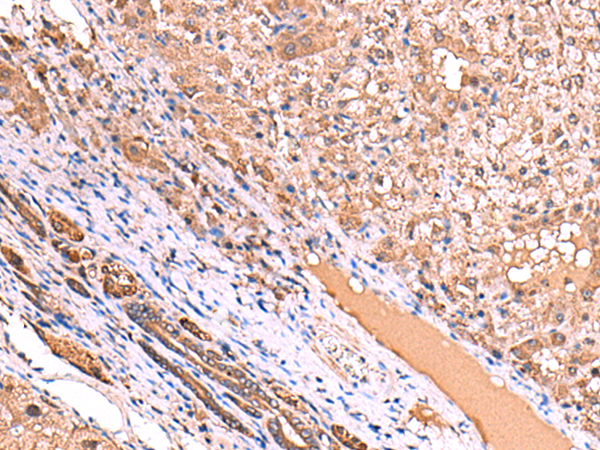

The image is immunohistochemistry of paraffin-embedded Human tonsil tissue using 47415(TTC38 Antibody) at dilution 1/85.(Original magnification: 200)

The image is immunohistochemistry of paraffin-embedded Human liver cancer tissue using 47415(TTC38 Antibody) at dilution 1/85.(Original magnification: 200)